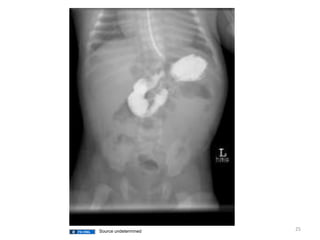

Necrotizing enterocolitis (NEC)

• Most common acquired gastrointestinal

• Intramural air, and may progress to frank

necrosis with perforation Sepsis/Death